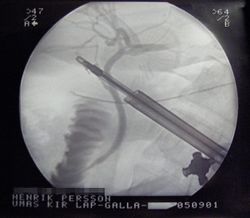

استعملت الأشعة السينية في مجالات الطب والصناعة، وكان الأطباأوالمستفيدين من استعمالها بسبب اختلاف نسب امتصاصها في الأنسجة الحية باختلاف نوع هذه الأنسجة، فاستخدمت خاصة الفلورة في التنظير الشعاعي ودراسة حركية الأعضاء، ثم استخدمت الدارة التلفزيونية في نقل الصورة المتفلورة إلى شاشة التلفاز الذي أصبح يستخدم في التنظير الشعاعي، وبذلك تناقصت كمية الأشعة اللازمة للحصول على الصورة المفلورة المتلفزة.

وكذلك استعملت الأشعة السينية في التصوير الشعاعي لمختلف أعضاء الجسم، ثم أدخل استعمالها مع الحواسيب للحصول على صور أكثر دقة وتفصيلاً للأعضاء المختلفة (أجهزة التصوير الطبقي المحوري). واستخدمت الأشعة السينية أيضاً في معالجة الأورام الخبيثة ومنع انتشارها، وجهد الفيزيائيون في زيادة قدرة نفوذها في الأنسجة المختلفة للجسم للوصول إلى الأورام العميقة، فاستعملت المسرعات الخطية التي أصبحت اليوم من أحدث أجهزة المعالجة الشعاعية. استخدمت الأشعة السينية أيضاً في الصناعة لكشف الهنات والشقوق في القوالب المعدنية والأخشاب المستعملة في صناعة الزوارق، كما ساعدت دراسة طيف امتصاص هذه الأشعة في المادة على جعل الأشعة السينية طريقة لكشف العناصر الداخلة في تركيب المواد المختلفة وتحليلها. وتستعمل في هذه الحالة الأشعة السينية التي تميز كل عنصر من العناصر الكيمياوية. تبين منذ السنوات العشر الأولى لاستعمال الأشعة السينية في الطب (التشخيص والمعالجة) أن هذه الأشعة لا تخلو من التأثيرات المؤذية. فقد عرف منذ البدء، عندما استخدمها الأطباء في التنظير الشعاعي لجبر كسور العظام، أنها تحدث حروقاً في أيدي الطبيب الفاحص وأن لها تأثيراً في خلايا نقي العظام والغدد التناسلية. وأظهرت الدراسات الخلوية الحيوية فيما بعد التأثيرات المؤذية للأشعة تسبب حتى بمقادير قليلة أحياناً تبدلات في صبغيات نواة الخلية الحية (طفرات) مع ما يتلو ذلك من تشوهات ولادية أو من اضطراب تكاثر هذه الخلايا وبالتالي موتها.